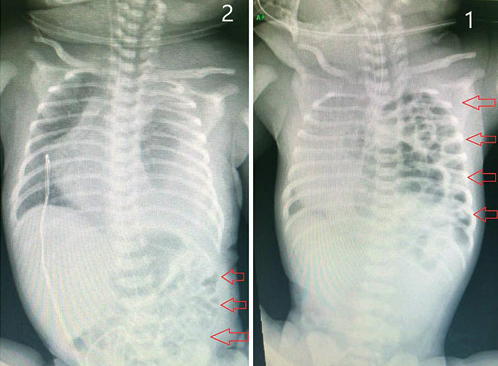

وأشار د.بطاينة إلى أنه بعد الاستقرار المبدئي لحالة الطفل تم تحويلة لقسم العمليات والبدء في إجراء جراحة استغرقت ساعة ونصف الساعة، وتم فيها عمل إعادة الأمعاء والطحال والكبد إلى التجويف البطني، ومن ثم زراعة شبكة متطورة للفصل ما بين التجويف البطني والتجويف الصدري. وعن حالة الطفل قال الدكتور زياد بطاينة إن العملية أجريت بنجاح تام ولله الحمد، حيث نقل الطفل للعناية الحثيثة للأطفال وهو في حالة مستقرة، وقد تم إجراء فحص بالأشعة على منطقة الصدر والبطن في اليوم الخامس للعملية وأظهرت الصور أمعاء البطن تعمل في تجانس تام وبصورة طبيعية، مشيراً إلى أنه تم إزالة الأنبوب بعد أسبوعين وأصبح يتنفس بصورة جيدة وخرج من المستشفى بعد ثلاثة أسابيع وهو بصحة جيدة ولله الحمد.